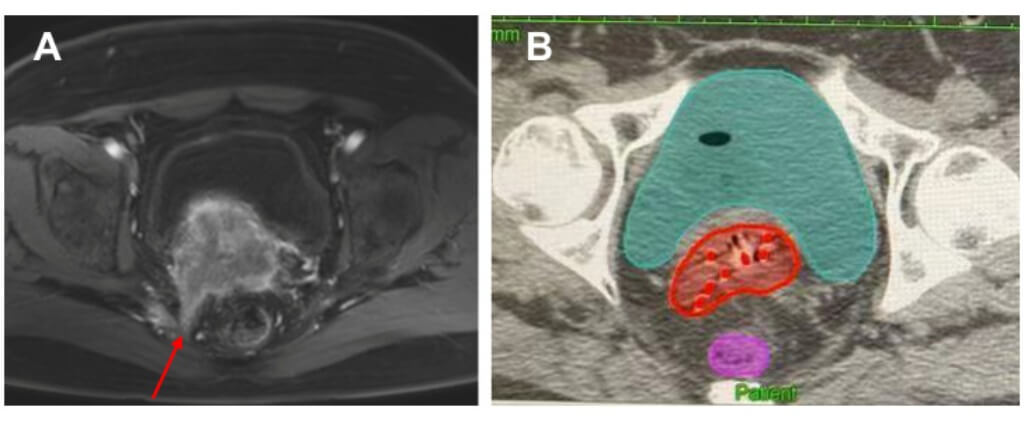

Before the start of internal radiation therapy, a detailed examination is carried out. Patients are subjected to pelvic MRI or CT scans, which enable specialists to see the cancer cells, define what size the tumor is, and where it is located precisely, as well as examine the state of other organs and healthy tissue. On the basis of these images, the treatment team develops a unique treatment plan. At this point, the radiation oncologist determines the best radiation dose and determines the type of applicator that should be used, whether it is an intracavitary brachytherapy or interstitial brachytherapy.

A major innovation is brachytherapy treatment guided by imaging. MRI or CT scans help locate the cancer cells precisely. This enables the treatment team and the radiation oncologist to come up with an individualized treatment plan that gives the best radiation dose to the tumor without necessarily sacrificing the surrounding organs.

Intracavitary brachytherapy and interstitial brachytherapy, planning with 3D software, are also used in modern clinics to enable a physician to customize treatment to the stage of cervix cancer and individual anatomy. In some cases, temporary brachytherapy or permanent brachytherapy is applied, offering flexible and individualized care.